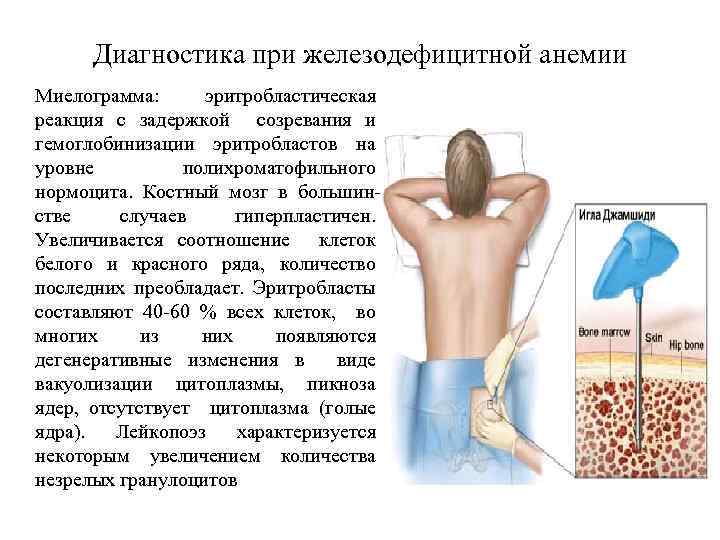

Диагностика при железодефицитной анемии Миелограмма: эритробластическая реакция с задержкой созревания и гемоглобинизации эритробластов на уровне полихроматофильного нормоцита. Костный мозг в большинстве случаев гиперпластичен. Увеличивается соотношение клеток белого и красного ряда, количество последних преобладает. Эритробласты составляют 40 -60 % всех клеток, во многих из них появляются дегенеративные изменения в виде вакуолизации цитоплазмы, пикноза ядер, отсутствует цитоплазма (голые ядра). Лейкопоэз характеризуется некоторым увеличением количества незрелых гранулоцитов